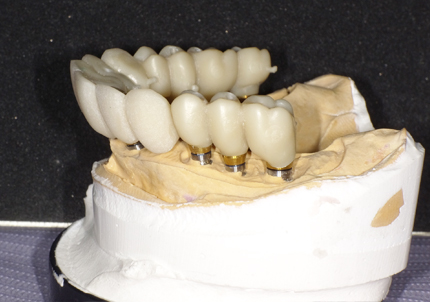

17.シリンダーテック作製(2019年10月)

側方から見て形状の確認

21.ジルコニアブリッジ試適(2020年12月)